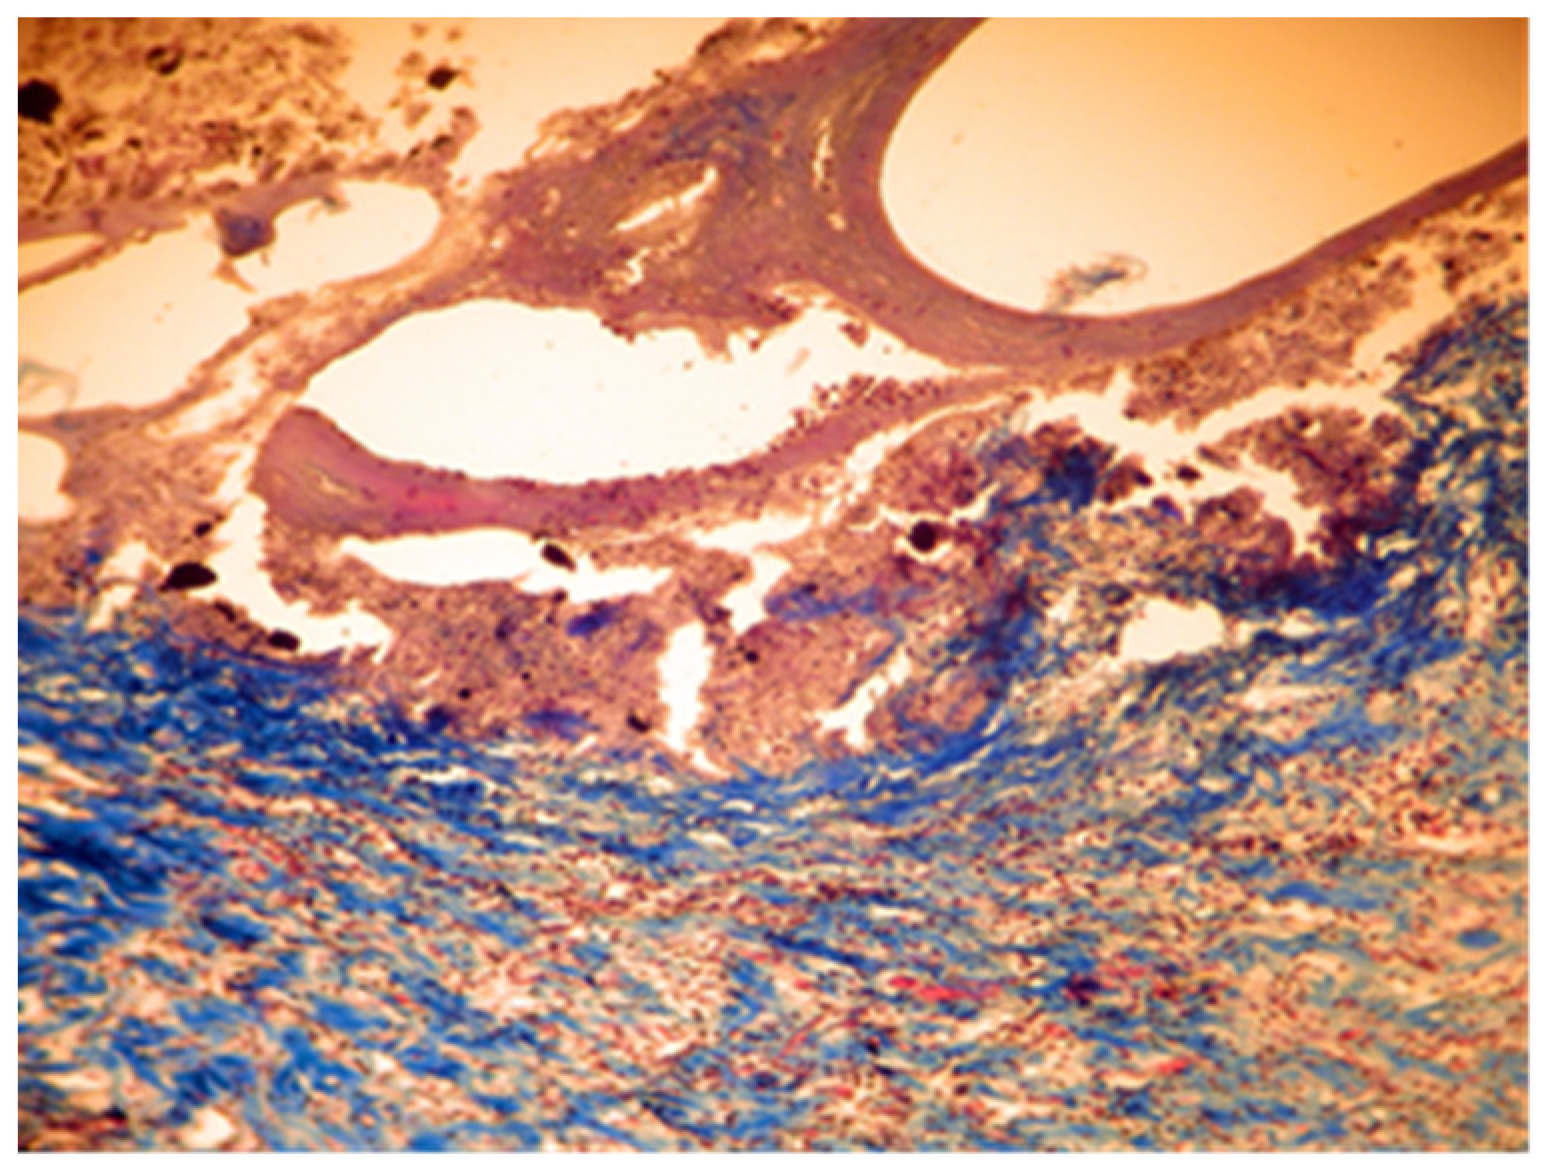

In samples collected 30 days after implantation, there was a significant decrease in local cellular reactions in all groups (A, B, and C), and inflammation was almost nonexistent, with rare inflammatory infiltrate cells being observed only in groups B and A (Figure 11 and Figure 12).

Figure 11. Group A. Scar tissue and rare inflammatory cells at the implant site with MTA after 30 days. Rare inflammatory cells. Col. Trichrome Masson, ×400.

Figure 12. Group B. Dense subcutaneous tissue over the implant with MTA after 30 days. Rare inflammatory cells. Col. Trichrome Masson, ×400.